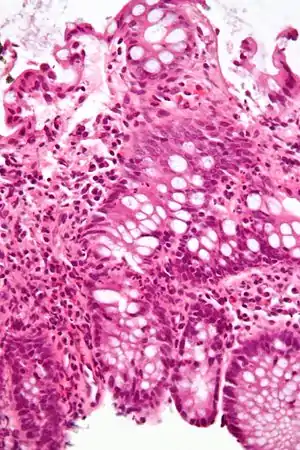

Micrograph of the small intestine mucosa showing the intestinal glands - bottom 1/3 of image. H&E stain.

In histology, an intestinal gland (also crypt of Lieberkühn and intestinal crypt) is a gland found in between villi in the intestinal epithelium lining of the small intestine and large intestine (or colon). The glands and intestinal villi are covered by epithelium, which contains multiple types of cells: enterocytes (absorbing water and electrolytes), goblet cells (secreting mucus), enteroendocrine cells (secreting hormones), cup cells, tuft cells, and at the base of the gland, Paneth cells (secreting anti-microbial peptides) and stem cells.

Structure

Intestinal glands are found in the epithelia of the small intestine, namely the duodenum, jejunum, and ileum, and in the large intestine (colon), where they are sometimes called colonic crypts. Intestinal glands of the small intestine contain a base of replicating stem cells, Paneth cells of the innate immune system, and goblet cells, which produce mucus.[1] In the colon, crypts do not have Paneth cells.[2]